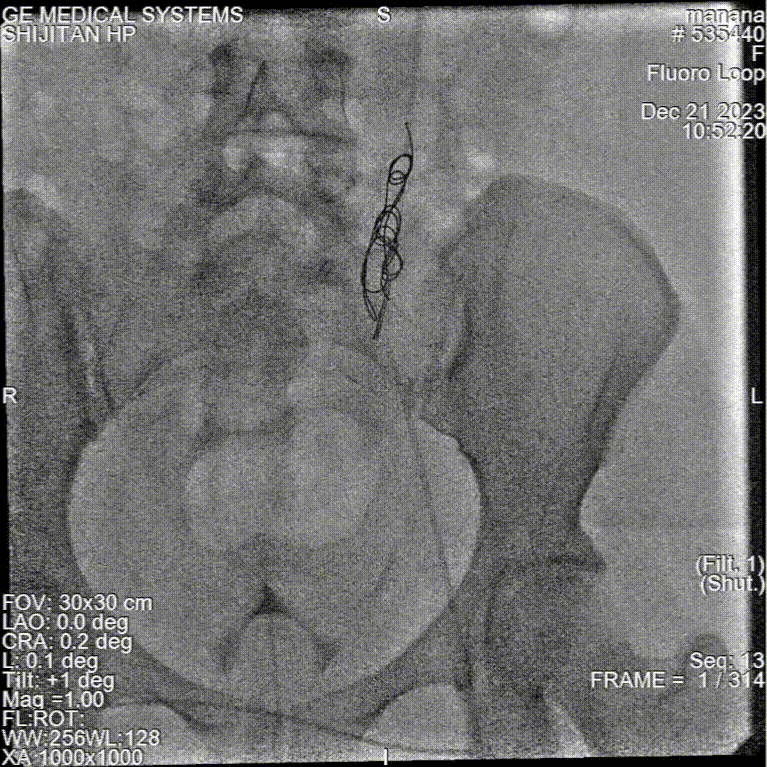

★ 卵巢静脉造影(诊断金标准)

尽管是侵入性操作,但静脉造影仍是诊断的“金标准”。其诊断标准(2019UIP)包括:

卵巢静脉直径 > 6 mm;

造影剂在盆腔静脉丛滞留 > 20秒;

盆腔静脉丛充血、迂曲,造影剂反流可越过中线;

可见同侧或对侧髂内静脉、外阴、阴道及大腿静脉曲张显影。